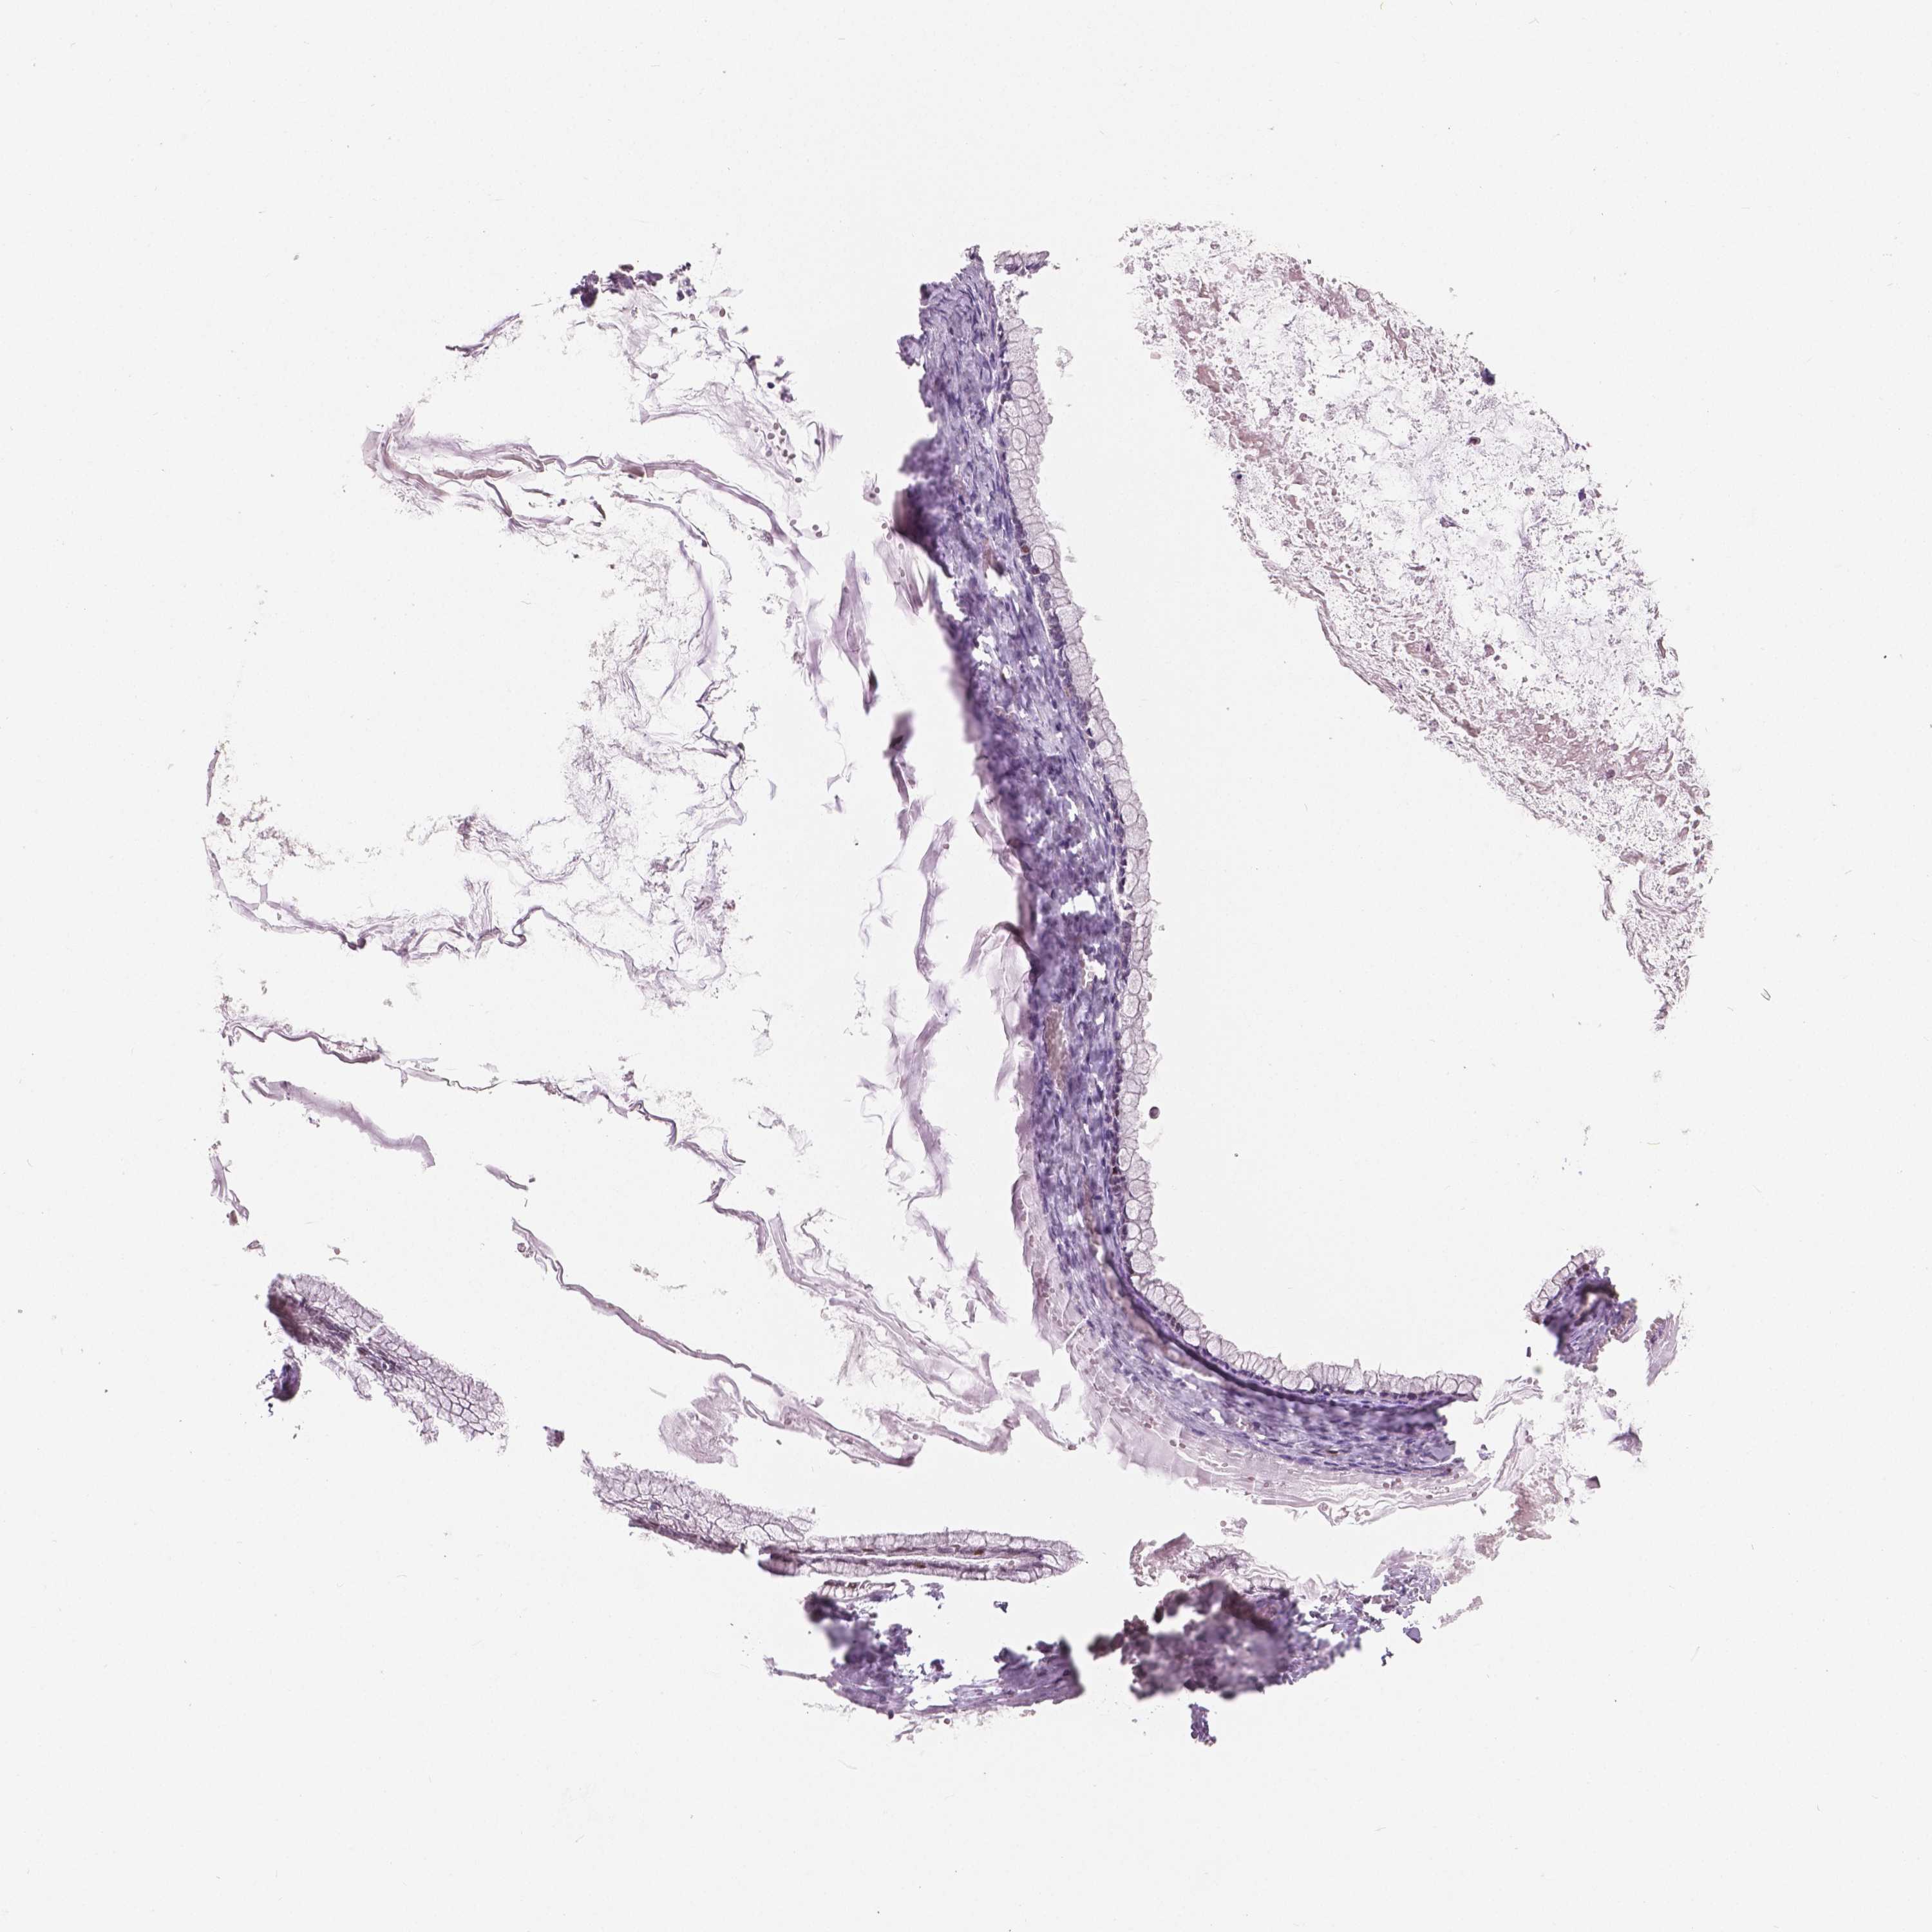

OVARIAN CANCER - Protein expressioni

A mouse-over function shows sample information and annotation data. Click on an image to view it in a full screen mode. Samples can be filtered based on level of antibody staining by selecting one or several of the following categories: high, medium, low and not detected. The assay and annotation is described here.

Note that samples used for immunohistochemistry by the Human Protein Atlas do not correspond to samples in the TCGA dataset.

Antibody stainingi

Antibody staining in the annotated cell types in the current human tissue is reported as not detected, low, medium, or high, based on conventional immunohistochemistry profiling in selected tissues. This score is based on the combination of the staining intensity and fraction of stained cells.

Each image is clickable and will lead to virtual microscopy that enables deeper exploration of all samples and also displays staining intensity scores, fraction scores and subcellular localization as well as patient and tissue information for each sample.

Antibody HPA015801

Antibody CAB068246

Antibody CAB068247

Staining

High

Medium

Low

Not detected

Cystadenocarcinoma, serous, NOS

Cystadenocarcinoma, mucinous, NOS

Carcinoma, endometroid